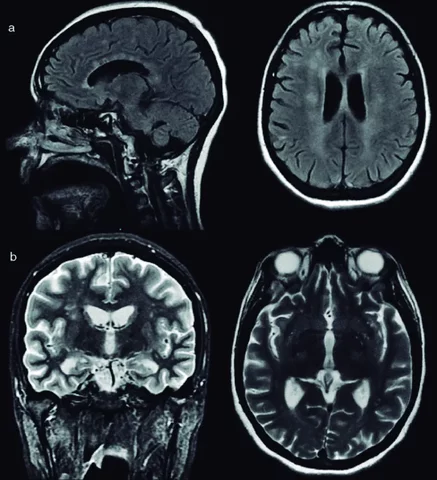

• Primera Tomografia de cerebro

Primera Tomografia de cerebro

Sin neccesidad de apertura de la cavidad craneal, se logro captar una imagen del craneo de una persona.